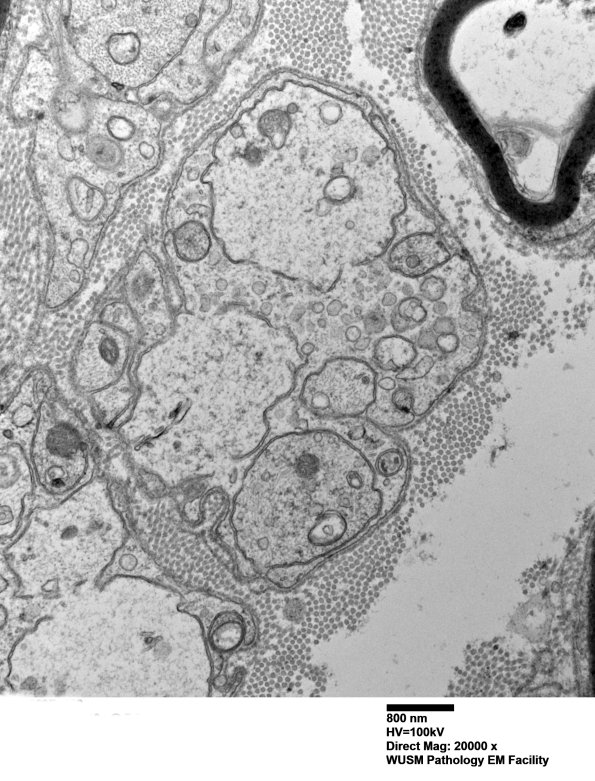

This pair of structures has similar appearance to the previously presented two axon-like forms. (electron micrograph)